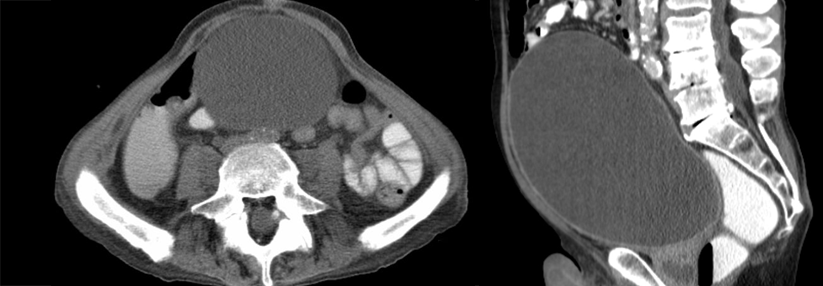

Zur Therapie gibt es verschiedene Verfahren: Die endoskopische Urethrotomie bietet nur für Betroffene mit primärer, kurzstreckiger (< 1 cm) bulbärer Striktur eine kurative Option und selbst bei diesen Patienten muss man mit einer Rezidivrate von rund 30 % rechnen. Bei penilen und glandulären Stenosen ist kein dauerhafter Erfolg zu erwarten. Stents werden heutzutage kaum noch eingesetzt, die Bougierung wirkt nur palliativ. Entscheidend für die Prognose ist der rechtzeitige Entschluss zur Operation. Denn mit der zunehmenden Zahl vorangegangener endoskopischer Therapien sinken die Erfolgsaussichten einer chirurgischen Sanierung. Bei bulbären Strikturen mit einer Ausdehnung > 1 cm ist die Urethroplastik das Verfahren der Wahl. Gleiches gilt für die penile oder glanduläre Lokalisation und für Rezidive. Der Eingriff führt in etwa 80– 95 % der Fälle zu langfristiger Rückfallfreiheit. Die besten Resultate erzielt die End-zu-End-Anastomose nach Exzision des fibrotisch veränderten Teils der Urethra. Sie eignet sich optimal für bulbäre Läsionen bis 2 cm Länge. Zu den potenziellen Komplikationen zählen Empfindungsstörungen und eine fehlende Füllung der Glans bei der Erektion. Für Patienten mit bulbärer Striktur über 2 cm, Rezidiv nach End-zu-End-Anastomose oder peniler bzw. penobulbärer Lokalisation empfehlen die Autoren die Graft-Urethroplastik.

Expansion mit Mundschleimhaut

Dabei wird die Harnröhre auf der gesamten Länge der Striktur eröffnet und durch ein Transplantat erweitert. Die Expansion mit Mundschleimhaut ist dem Einsatz von Vorhautgewebe überlegen. Patienten nach Radiatio können von einer Flap-Urethroplastik profitieren. Die besonders schwierige Harnröhrenrekonstruktion nach fehlgeschlagener Hypospadiekorrektur sollte nur in spezialisierten Zentren erfolgen. Für Männer mit vollständig destruierter Harnröhre (z.B. nach Stentimplantation) kommt als Ultima Ratio eine perineale Urethrostomie in Betracht. Mit diesem Eingriff lassen sich Harnröhrenstrikturen jeder Form zuverlässig ausschalten. Allerdings ist danach eine Miktion auf natürlichem Weg ebenso wenig möglich wie eine normale Ejakulation. Quelle: Tritschler S, Beck V. Urologe 2021; 11: 1473- 1479; DOI: 10.1007/s00120-021-01692-5